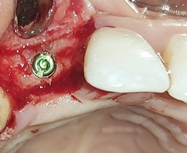

On the day of implant placement : (Figures 6,7). The implant was placed 7 years after the fall of 12 (loss of tooth due to trauma) in a completely healed site. 10 days after implant placement: (Figure 8). A temporary mesially extended bridge supported on 13 was cemented .

Figure 6 Placement of the implant + screw cover + suture.

Figure 7 Postoperative retro alveolar radiograph on the day of implant placement.